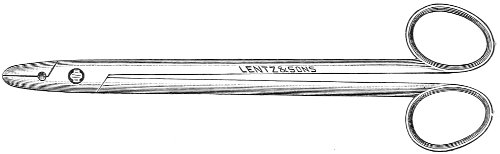

Fig. 24.—Emmet’s perineal scissors.

Fig. 25.—Curved scissors for denuding.

The secondary operation is performed at any time after cicatrization has occurred—often many years after the receipt of the injury. This operation is at present one of the commonest in gynecology, because the injury is not detected, is neglected, or is improperly repaired after labor. In the secondary operation an anesthetic is necessary. The mucous membrane must be removed or denuded on the posterior wall and about the mouth of the vagina, in order that the lacerated structures may be brought again in apposition. The denudation is best made by means of scissors curved on the flat (Figs. 24 and 25).

The strip of mucous membrane to be removed is picked up with a tenaculum (Fig. 26) or with tissue forceps 65 (Fig. 27); the scissors are placed with the blades parallel to the surface to be denuded, and the strip is cut away evenly, in one piece if possible. A similar contiguous strip is removed, and so on until the necessary surface is bare. Sponges in holders (Fig. 28) or continuous irrigation may be used to remove blood.